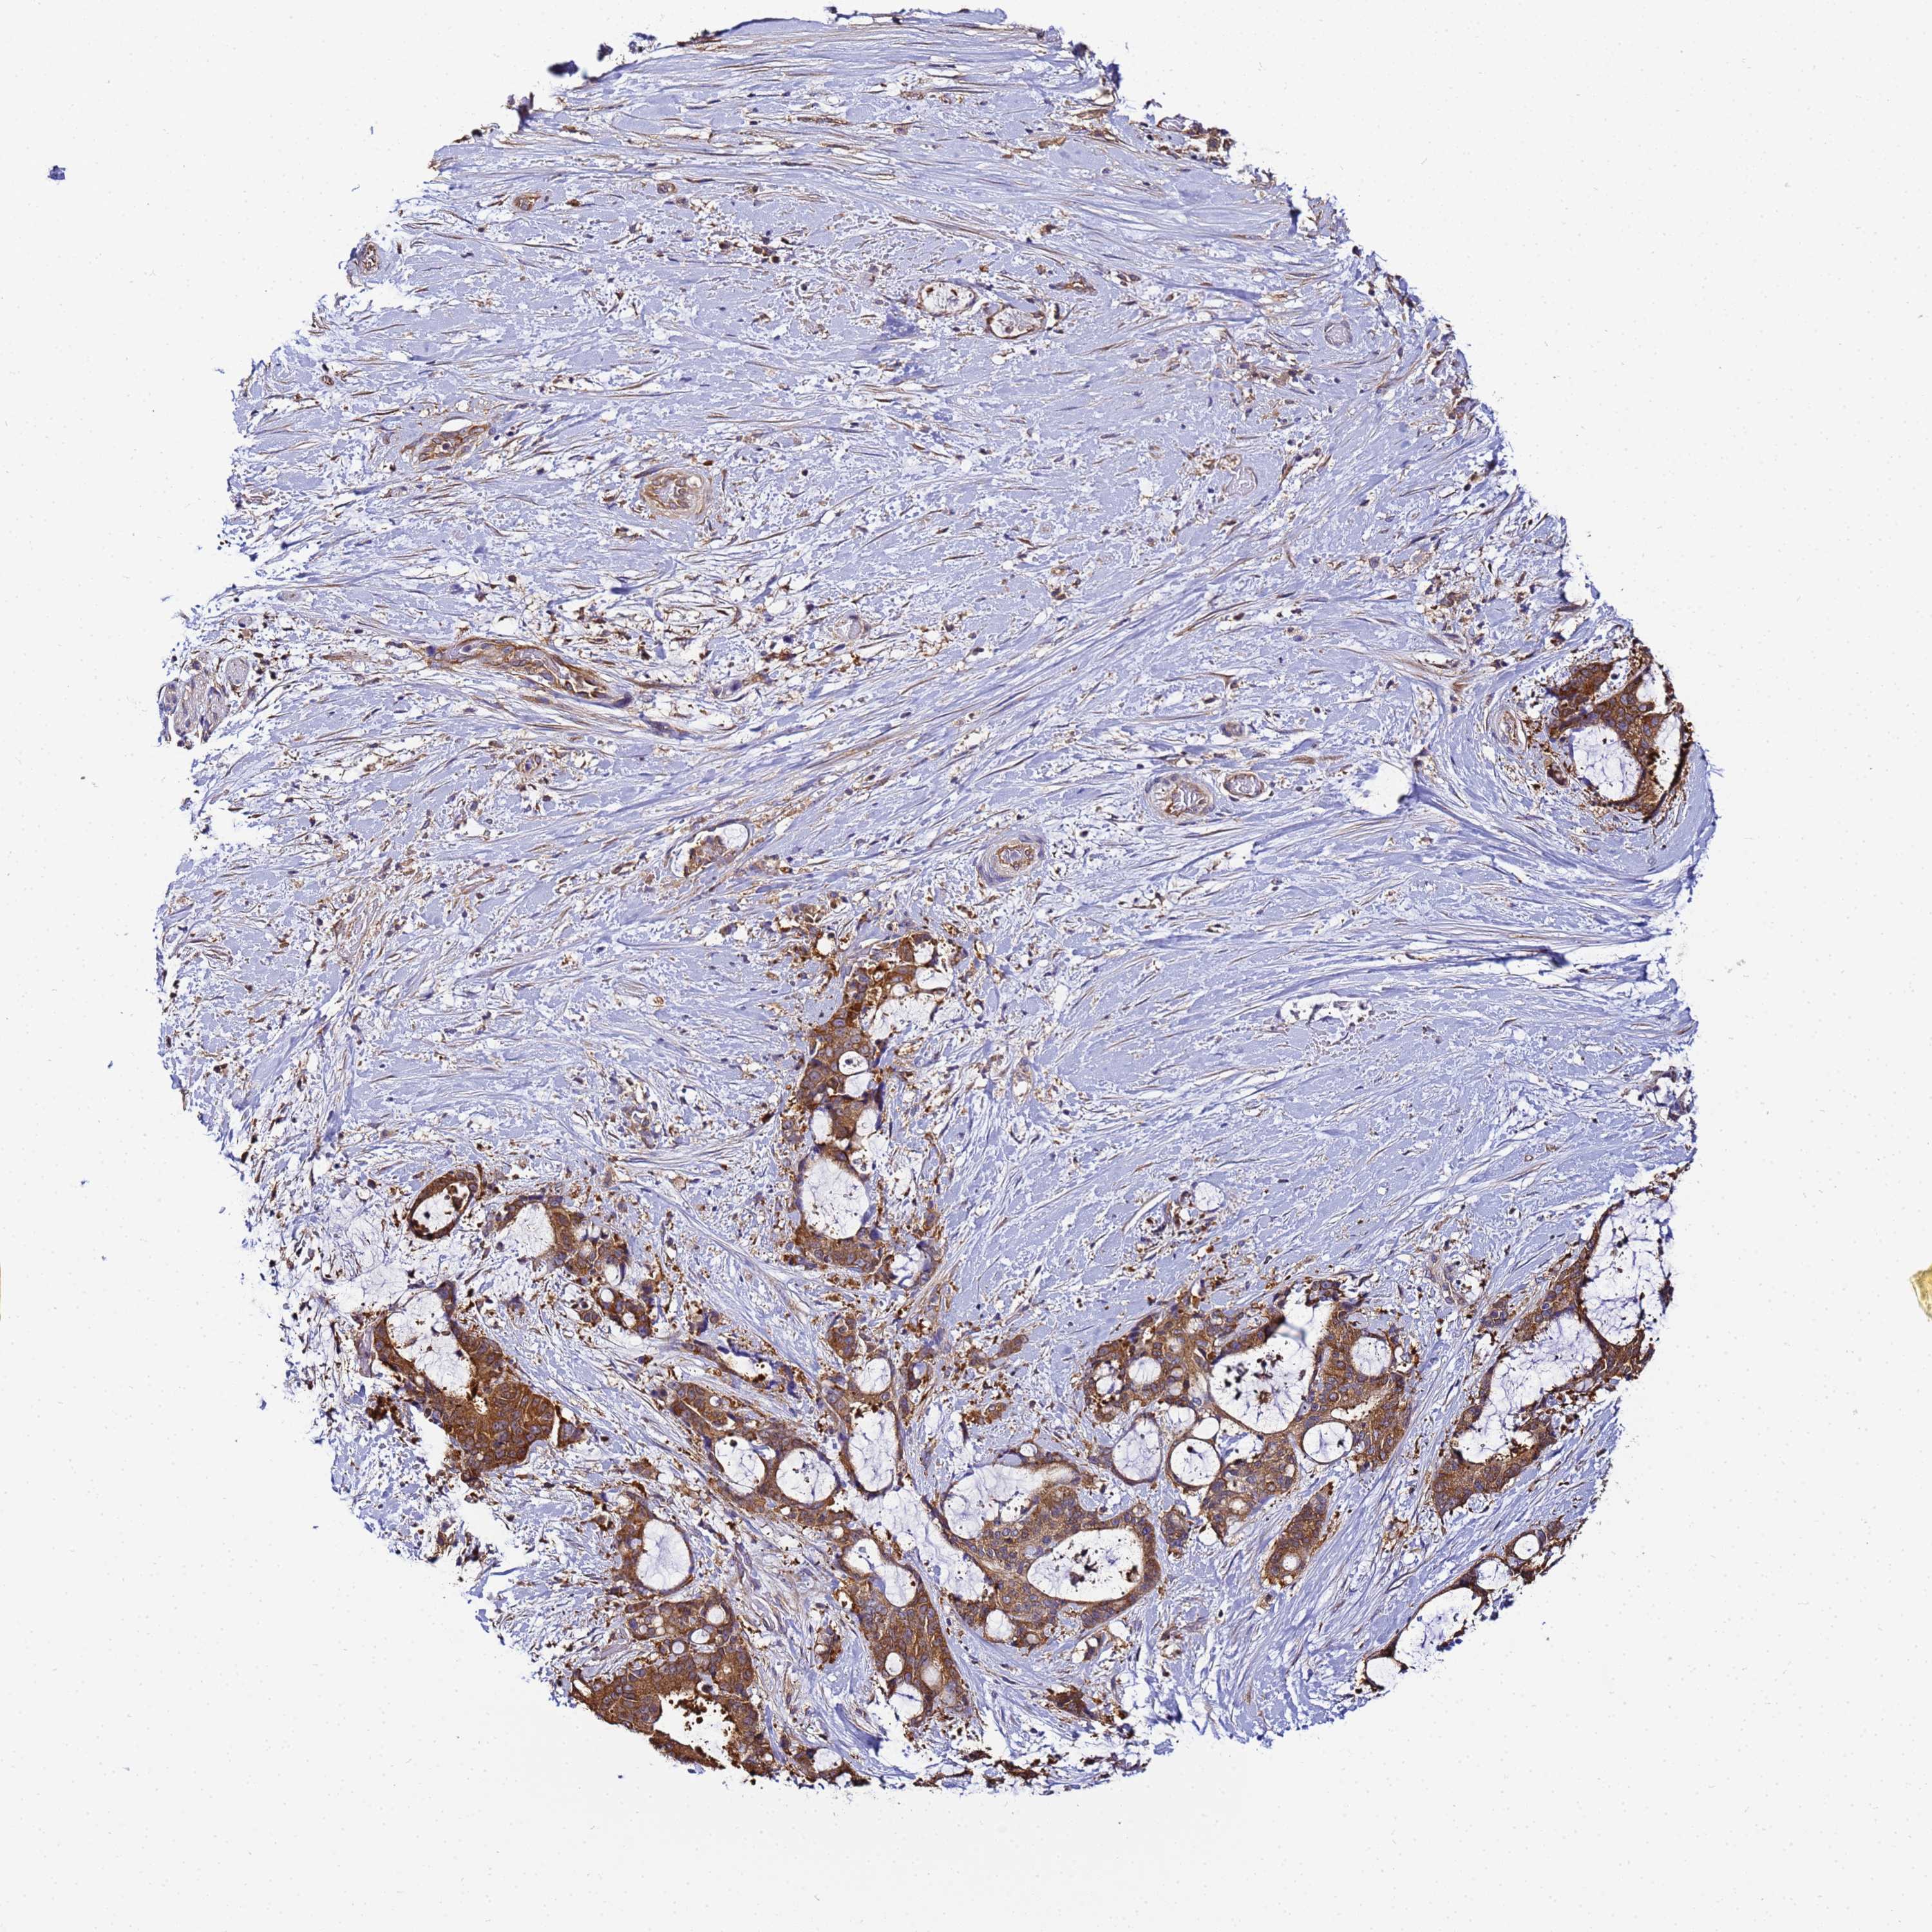

LIVER CANCER - Protein expressioni

A mouse-over function shows sample information and annotation data. Click on an image to view it in a full screen mode. Samples can be filtered based on level of antibody staining by selecting one or several of the following categories: high, medium, low and not detected. The assay and annotation is described here.

Note that samples used for immunohistochemistry by the Human Protein Atlas do not correspond to samples in the TCGA dataset.

Antibody stainingi

Antibody staining in the annotated cell types in the current human tissue is reported as not detected, low, medium, or high, based on conventional immunohistochemistry profiling in selected tissues. This score is based on the combination of the staining intensity and fraction of stained cells.

Each image is clickable and will lead to virtual microscopy that enables deeper exploration of all samples and also displays staining intensity scores, fraction scores and subcellular localization as well as patient and tissue information for each sample.

Antibody HPA040017

Antibody CAB034257

Staining

High

Medium

Low

Not detected

Intensity

Strong

Moderate

Weak

Negative

Quantity

>75%

75%-25%

<25%

None

Location

Nuclear

Cytoplasmic/membranous

Cytoplasmic/membranous,nuclear

Cholangiocarcinoma

Carcinoma, Hepatocellular, NOS